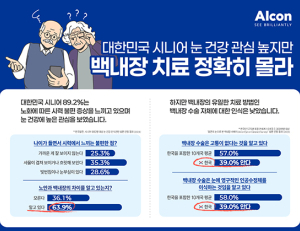

- 시니어, 눈 건강 관심 높지만 백내장 치료 인식은 부족

- 글로벌 안과 전문기업 알콘(Alcon)의 한국 지사인 한국알콘이 국내 시니어의 눈 건강 인식과 백내장 치료에 대한 이해 수준을 파악하기 위해 실시한 조사 결과...

- 2024-11-07